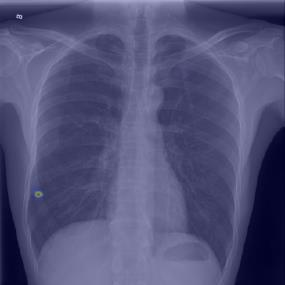

Chest X-ray (CXR) is the most typical diagnostic X-ray examination for screening various thoracic diseases. Automatically localizing lesions from CXR is promising for alleviating radiologists' reading burden. However, CXR datasets are often with massive image-level annotations and scarce lesion-level annotations, and more often, without annotations. Thus far, unifying different supervision granularities to develop thoracic disease detection algorithms has not been comprehensively addressed. In this paper, we present OXnet, the first deep omni-supervised thoracic disease detection network to our best knowledge that uses as much available supervision as possible for CXR diagnosis. We first introduce supervised learning via a one-stage detection model. Then, we inject a global classification head to the detection model and propose dual attention alignment to guide the global gradient to the local detection branch, which enables learning lesion detection from image-level annotations. We also impose intra-class compactness and inter-class separability with global prototype alignment to further enhance the global information learning. Moreover, we leverage a soft focal loss to distill the soft pseudo-labels of unlabeled data generated by a teacher model. Extensive experiments on a large-scale chest X-ray dataset show the proposed OXnet outperforms competitive methods with significant margins. Further, we investigate omni-supervision under various annotation granularities and corroborate OXnet is a promising choice to mitigate the plight of annotation shortage for medical image diagnosis.